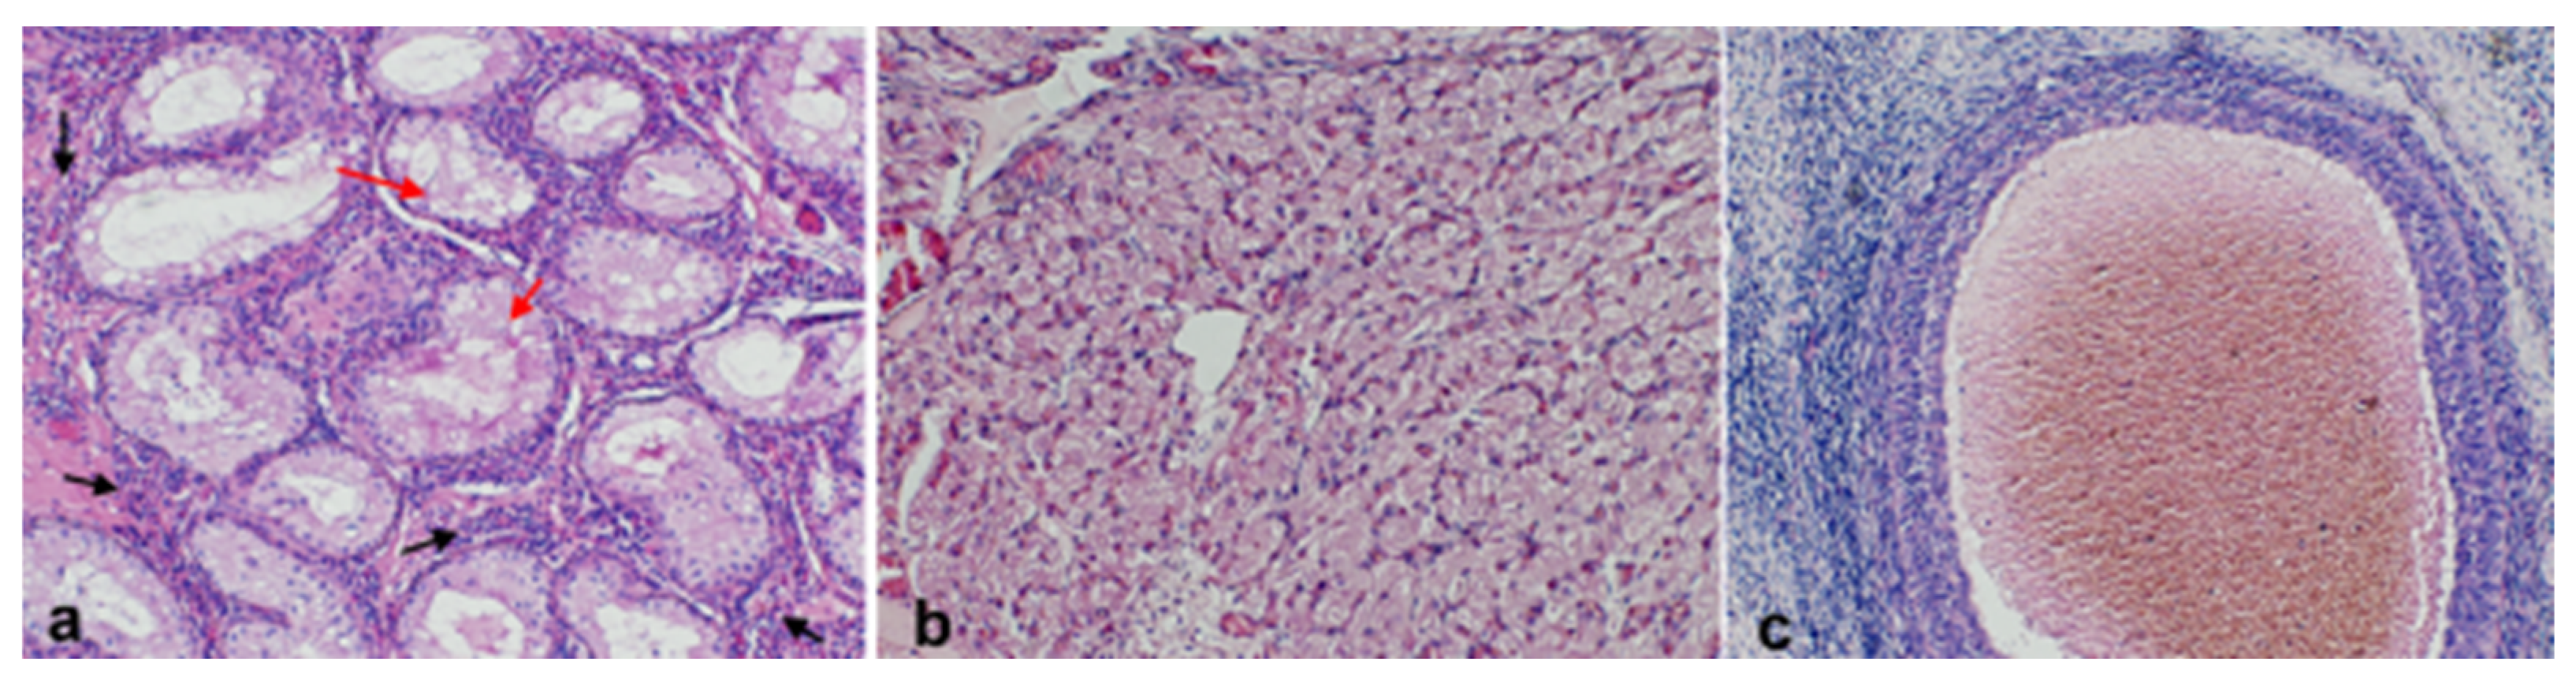

2.2. Histopathology